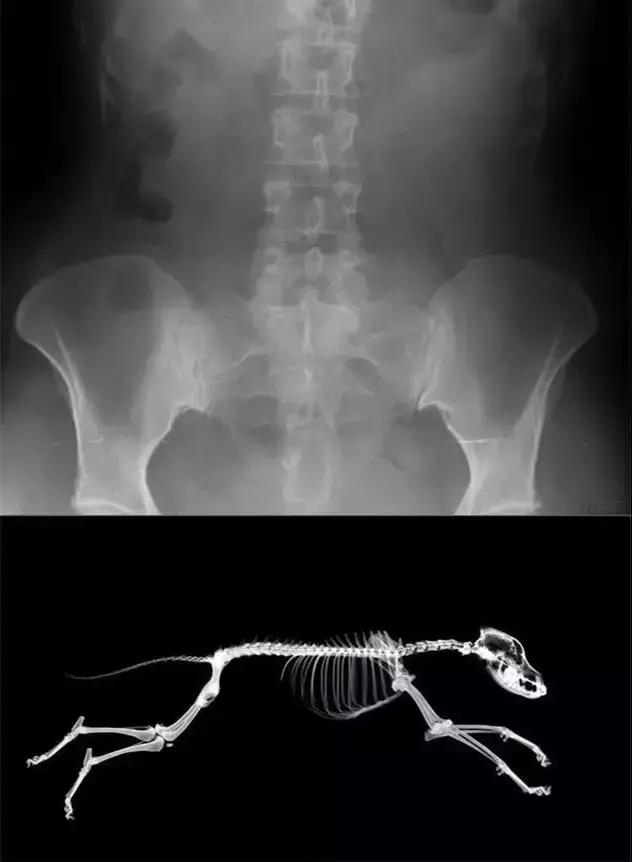

人能两条腿走路,是因为天生的骨骼构造如此,脊柱、髋关节、后腿都能承受较大的压力,和狗狗的构造差异很大。

狗狗后腿对身体的支撑主要是靠股骨头契合髋关节(即骨盆部位),当狗狗站立时,髋关节会承受巨大的压力,容易导致髋关节部位血液循环受到阻碍。直立走路的时间一久,容易发生股骨头脱位、股骨头坏死、髋关节异常、软骨磨损等疾病。

狗狗的脊柱原来应该是和地面平行的,承受能力远远不如人类,直立行走会让身体的重量纵向分担到脊椎上,时间长了会导致脊椎变形、髓腔缩小、压迫神经等病情。严重的话还会导致后腿瘫痪甚至全身瘫痪……

脊椎伤害也不排除发生在颈椎(虽然直立行走通常不会直接对颈椎产生影响,但凡事无绝对),那么最严重的就会导致四肢瘫痪。